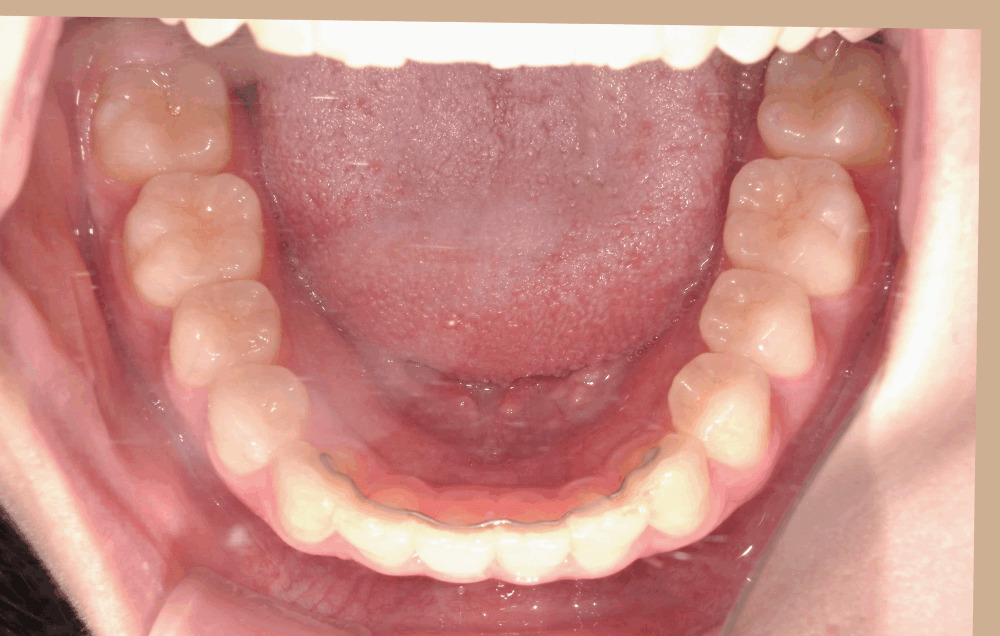

治療後の写真では、歯並びのガタつきが整い、前歯の角度も自然に改善されています。

Eラインに対してもバランスが取れ、力を入れなくても唇を閉じられる、リラックスした口元になりました。

治療前後の比較

治療前

治療後(15か月)

叢生、上顎前突を解消。正中線のずれも改善し、噛み合わせが良くなりました。 ※治療結果は患者様によって個人差があります。 |